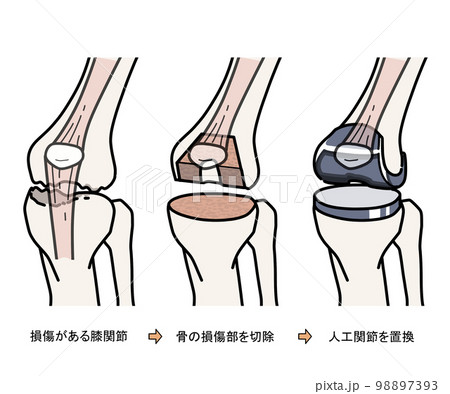

人工膝関節置換術 Total Knee Arthroplasty 全人工膝(ひざ)関節置換術(Total Knee Arthroplasty:TKAの詳細情報

全人工膝(ひざ)関節置換術(Total Knee Arthroplasty:TKA。COPYRIGHT UNION HOSPITAL 手術資料。Total knee replacement surgery (TKA) - Stock Illustration。人工膝関節置換術に関する専門的な内容を網羅した書籍。。关节置换术(膝关节置换)| 伊丽莎白医院。- タイトル: 人工膝関節置換術- サブタイトル: Total Knee Arthroplasty- 出版社: 南江堂- 定価: 1800円ご覧いただきありがとうございます。